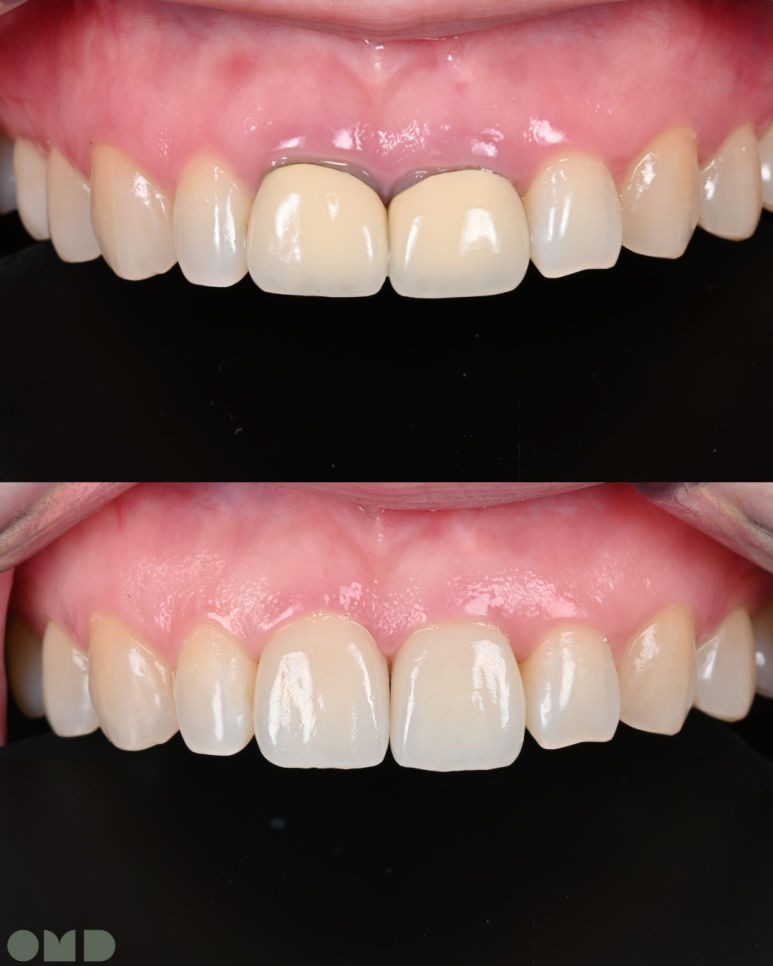

25.09.11 치료 후

앞니 크라운은 심미적으로 가장 눈에 띄는 부위라

작은 차이에도 만족도가 크게 달라집니다.

이번 케이스는 단순히 빠르게 크라운을 교체하는 대신

재신경치료 -> 임시치아 단계 -> 잇몸회복 -> 최종 크라운 이라는 단계를 차근차근 밟아갔습니다.

치료 기간은 거의 한달이 걸렸지만, 그만큼 안정적이고 자연스러운 결과를 얻을 수 있었습니다.